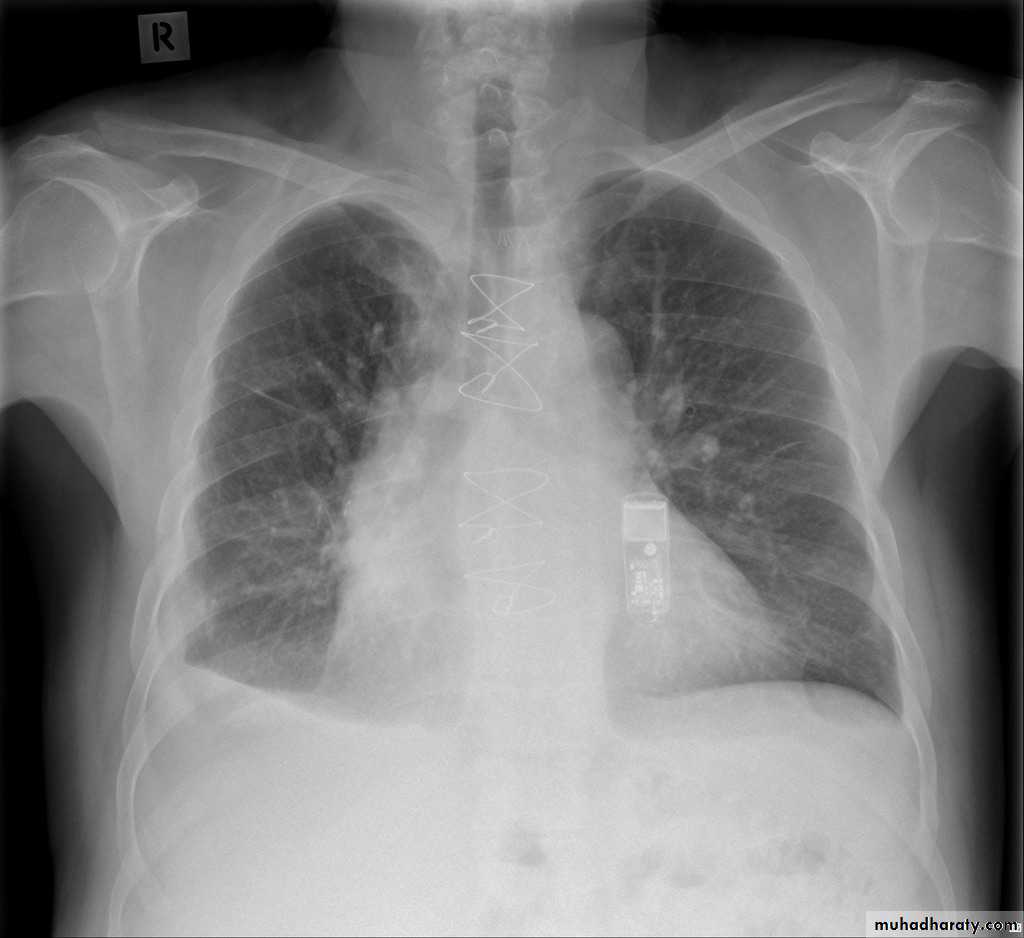

Left lower lobe collapse has distinctive features, and can be readily identified on frontal chest radiographs, provided attention is paid to the normal cardiomediastinal contours. The shadow cast by the heart does however make it harder to see than the right lower lobe collapse

Radiographic features

Left lower lobe collapseis readily identified in a well penetrated film of a patient with normal sized heart, but can be challenging in the typical patient with collapse, namely unwell patients, with portable (AP) often under-penetrated films, often with concomitant cardiomegaly. Features to be observed include :

triangular opacity in the posteromedial aspect of the left lung

edge of collapsed lung may create a 'double cardiac contour'

left hilum will be depressed

loss of the normal left hemidaphgragmatic outline

loss of the outline of the descending aorta

Non-specific signs indicating left sided atelectasis are usually also be present including:

elevation of the hemidiaphragm

crowding of the left sided ribs

shift of the mediastinum to the left

On lateral projection the left hemidiaphragmatic outline is lost posteriorly and the lower thoracic vertebrae appear denser than normal (they are usually more radiolucent than the upper vertebrae) .